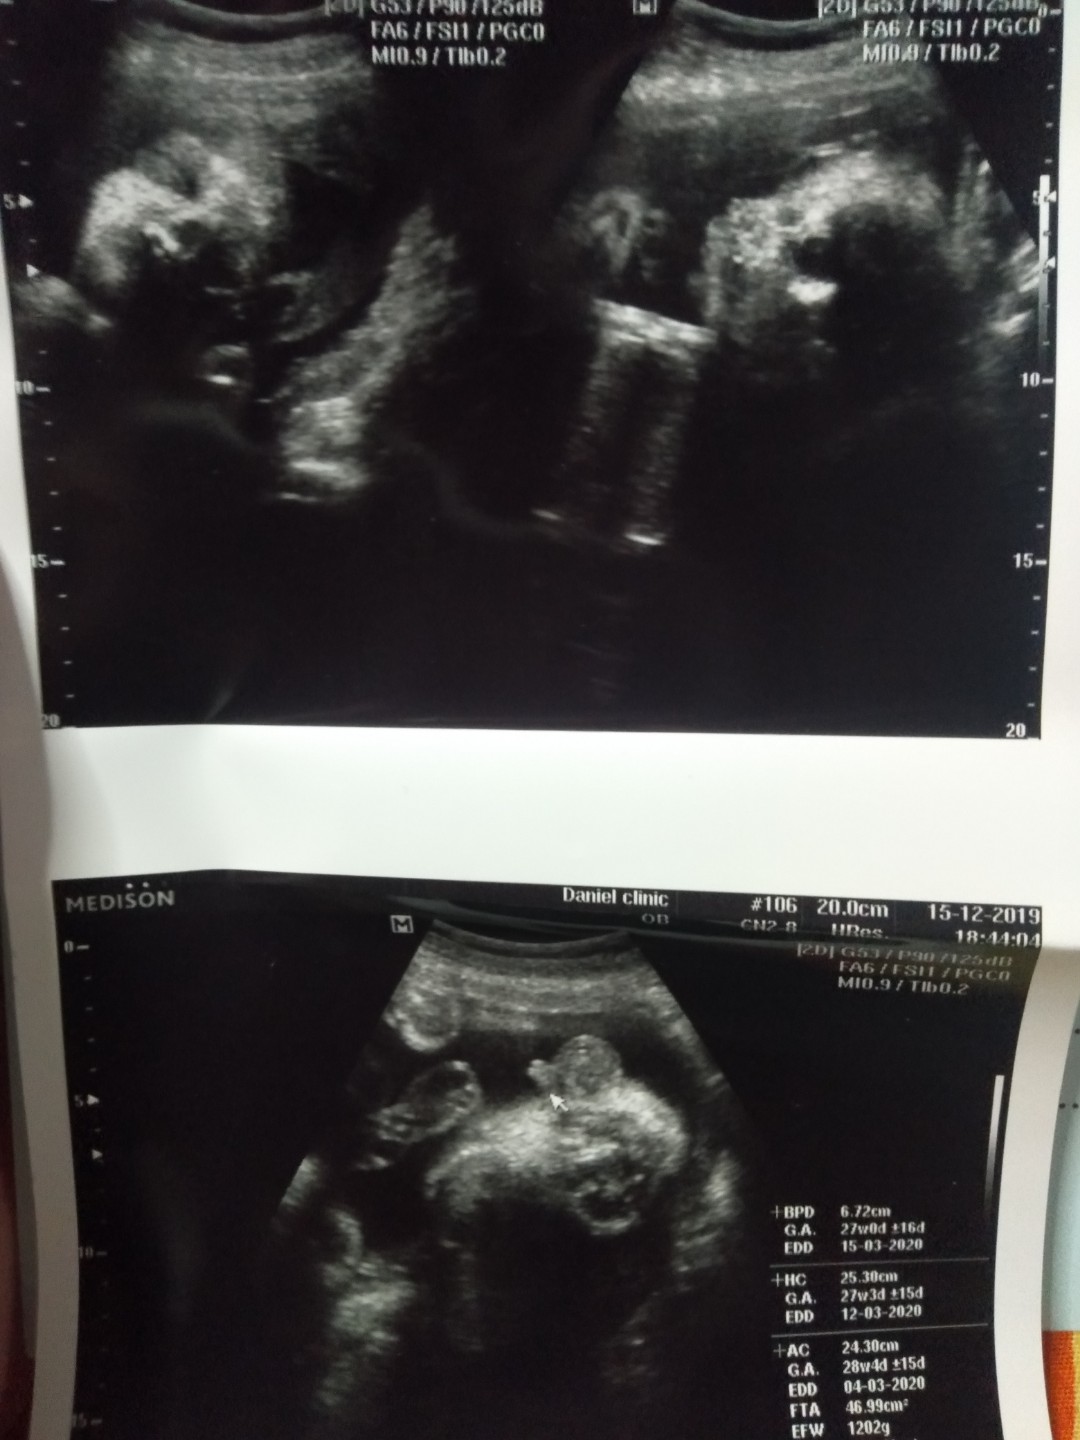

พึ่งซาวด์วันนี้ค่ะ อยากได้ผช. ได้สมใจ ?❤️?